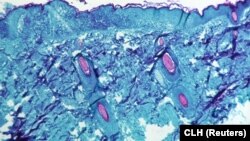

Imagine la microscop al unui țesut cutanat al unei maimuțe infectate. 1968